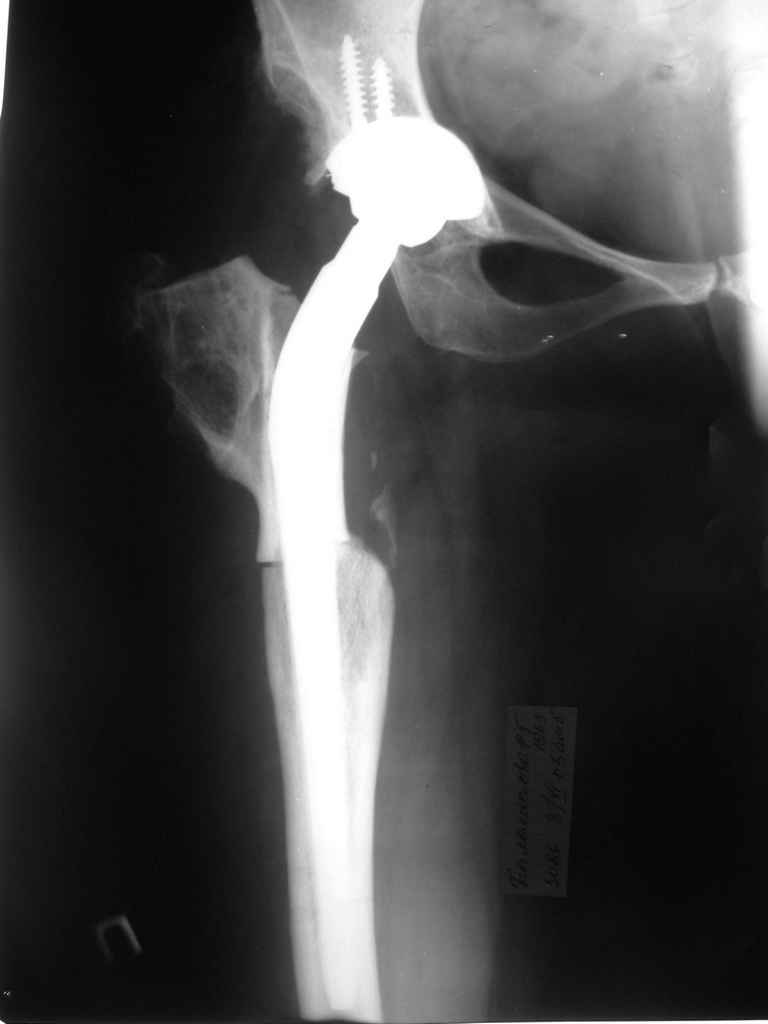

Moghno i tak kak sdelali my: pelvic support + tibial and equinus correction .

Слайд 1

Слайд 2

Слайд 3

Слайд 4

Devushka predstavlennaya na snimke nachala s LLD 9 cm, valgus deformation of the tibia, huge Trendelenburg( vidno na snimke).

Seichas : no LLD ,no Trendelenburg, reasonable hip motion.A samoe glavnoe ei ne predstoit kaghdye 10-15 let delat revision THR.

остеотомии. Я представил Р-граммы больных с неудачными р-ми после остеотомий.

Эндопротезирование у них было на порядок сложнее в отличие от артропластики без проведения остеотомии.